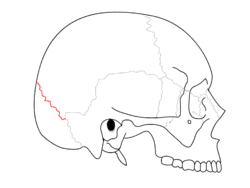

Lambdoid suture.png

Lambdoid suture (shown in red line)

The lambdoid suture (or lambdoidal suture) is a dense, fibrous connective tissue joint on the posterior aspect of the skull that connects the parietal bones with the occipital bone. It is continuous with the occipitomastoid suture.

Its name comes from its uppercase lambda-like shape.